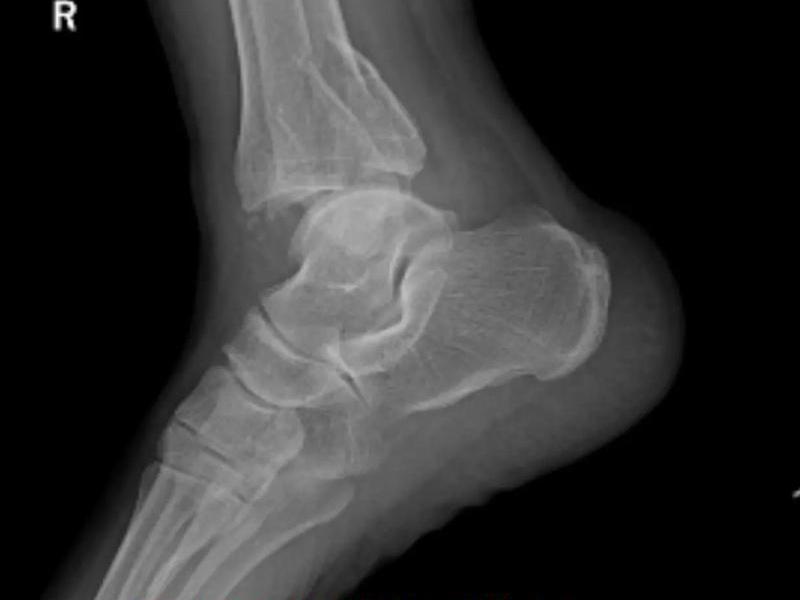

这几天,北京、武汉、南京、合肥等地普降大雪,因路面湿滑导致滑倒摔伤人群增加,不少医院里骨科、急诊接诊人数持续增加。北京大学第一医院骨科常务副主任孙浩林说,因雨雪天摔倒就诊的患者伤情多集中于手腕、髋骨和踝关节骨折,尤其是一些老年患者因骨质疏松,摔伤后需及时接受进一步治疗。

万一摔倒了,哪些情况可能是骨折了?公茂琪提示,在摔倒情况下,不要立即站起,应该先确认自己的肢体是否能够正常活动,身体躯干是否出现严重的疼痛,四肢是否发生严重的翻转、肿胀,及时就诊:

首都医科大学附属北京积水潭医院创伤骨科主任 公茂琪:一般讲究“先固定再搬运快就医”,你别移动受伤的部位,也别揉搓、推拉,因为会加重骨折的移位,甚至严重的骨折(很锐利的情况下)会损伤周围的神经血管,要求快速的固定,身边有什么就借用什么,譬如你带着书本,甚至什么都没有把围巾缠一缠轻轻地固定这个受伤部位,手指头能伸进去一个手指就可以了,然后赶快拨打120;譬如说要是胯骨骨折了,因为是比较严重的,就不要大动了,让病人就是平躺在担架上,也别让病人再起身翻身的,到了医院里,根据这个情况由医生来处理,是比较适宜的。